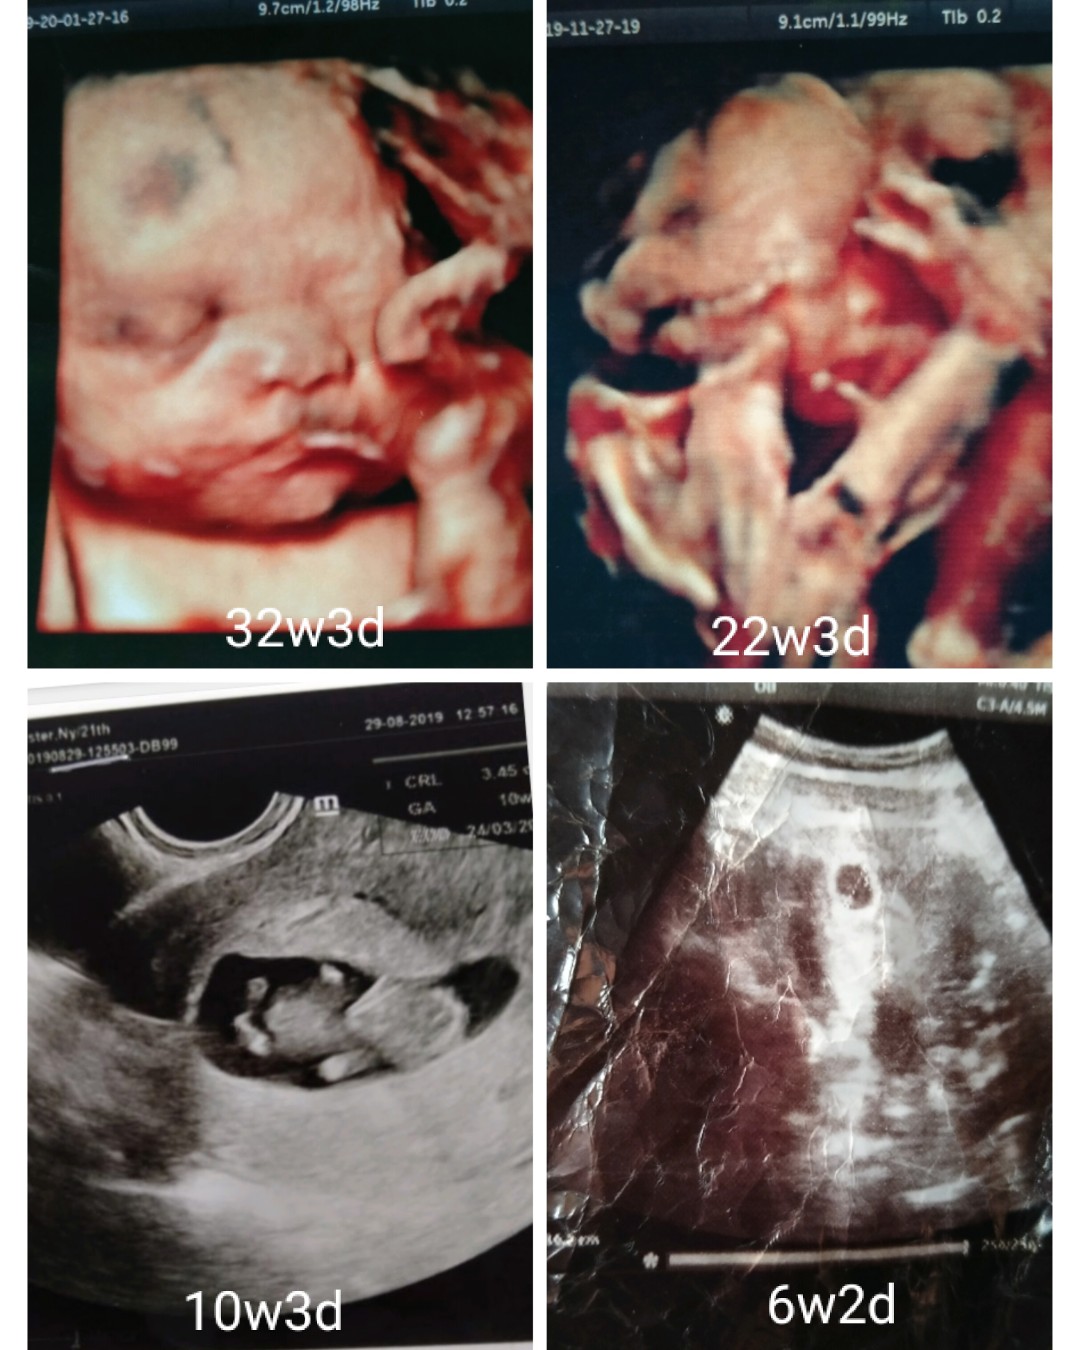

6w apakah masih kantong

bun mau tanya, perkiraan kan ini 6 minggu, masih kantong belum ada titik putih, apakah memang di usia segini belum muncul? mohon infonyaaaa ??

Wajar bun.. Nanti pas 9/10 w dede utun dh kelihatan kok insya Allah

Wajar Bun..waktu saya USG juga 5week baru kantong nya yg kelihatan

Iyaa bun memang kalo usia sgtu baru ngebentuk kantung janin ajaaa

Nunggu 2 minggu lagi bun pasti ada janin nya. Pengalaman ku gitu

Saya kemarin 6w memang kantong tp sudah ada titik putih nya bun

Saya 6 w baru keliatan kantong bun, 10 w udah keliatan janinnya

Saya 9w minggu keliatannya bun, 6w cuma keliatan kantongnya aja

Aku pas 6w udh keliatan isi nya bun tp usg nya transvaginal

8w bun mulai ada nnti 10w kalo pkek transv udh brbntuk bayi

ini saya waktu usg 6w bund baru kantong ny aja yg keliatan